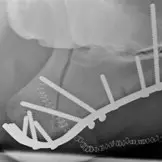

Fesselbeinfrakturen treten häufig als Stressfrakturen in der Mitte des Fesselbeines auf und können mit günstigen Heilungsaussichten verschraubt und zusätzlich gegipst werden.

Haarrisse im Fesselbein (Fesselbeinfissur) können in der Regel mit Boxenruhe und gegebenenfalls bei unruhigen Pferden mit Gipsfixation versorgt werden. Diese Fesselbeinfissuren haben meist gute Heilungsaussichten.